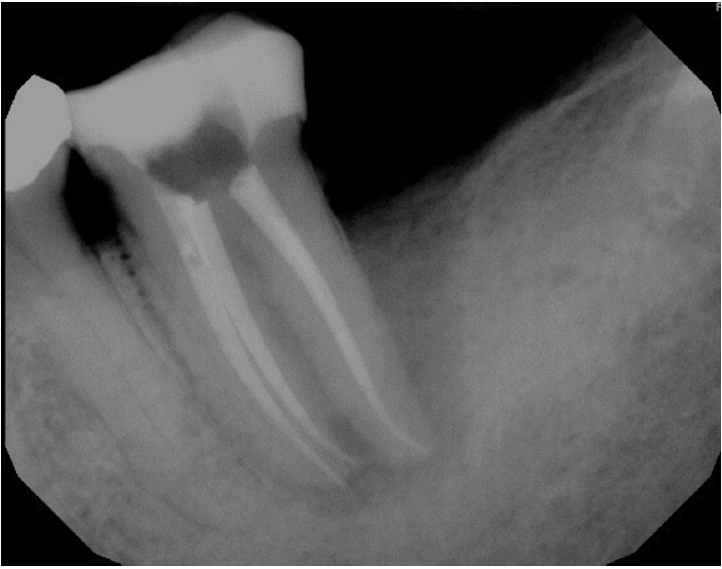

At the 2-week follow-up, the sinus tract had healed. After the same anesthesia and isolation protocol as the first visit, the tooth was accessed through the temporary restoration. Calcium hydroxide was irrigated out with 17% ethylenediaminetetraacetic acid solution, which was ultrasonically activated for 15 seconds in each canal. This was followed by 5% sodium hypochlorite irrigation, which was ultrasonically activated for 15 seconds in each canal, after which cone fit was verified clinically and confirmed with a radiograph (Figure 3). The canals were then dried with paper points, and obturation was completed using gutta-percha cones and AH Plus sealer (Dentsply DeTrey GmbH, Konstanz, Germany) with the cold lateral condensation technique. The tooth was temporized with a sterile sponge and Cavit (3M ESPE) and a postoperative radiograph was captured (Figure 4). A referral for periodontal therapy was given to the patient.

Figure 4.

Immediate postoperative radiograph.

rde-2025-50-e31f4.jpg

Figure 4. Immediate postoperative radiograph.